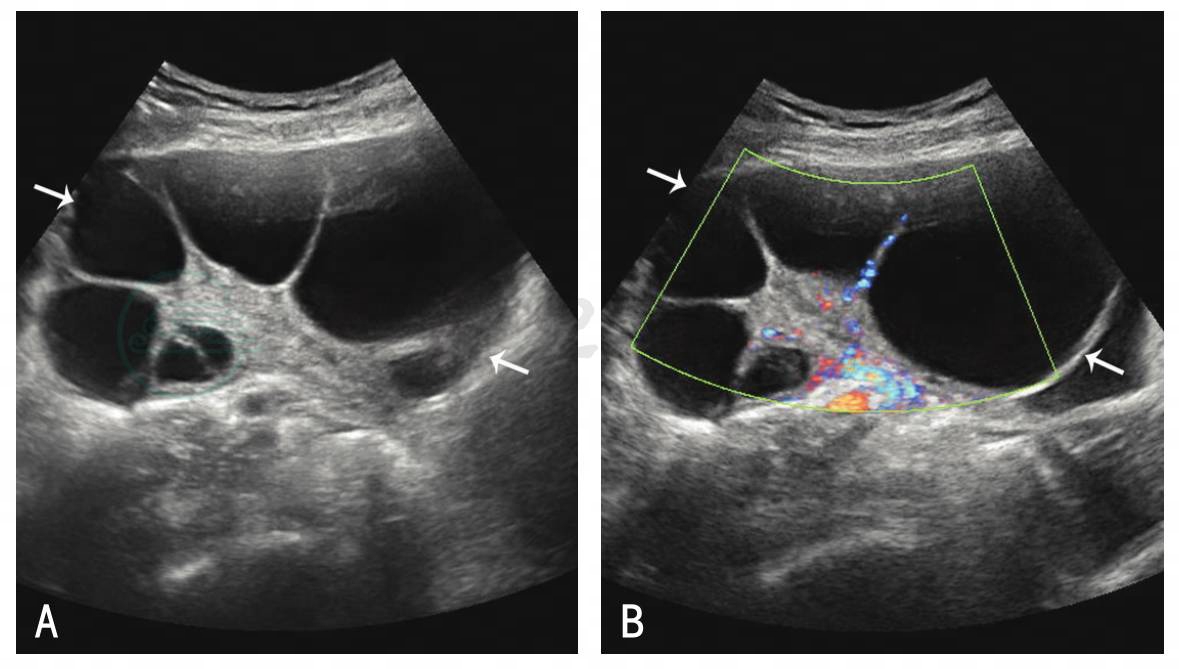

卵巢明显增大,卵巢内因含大量大小不等的卵泡和黄素化囊肿,呈多房囊肿样改变。囊壁菲薄,囊腔形态因相互挤压而不规则,囊内多为液性无回声,囊腔大小一般在2~6cm。轻度OHSS卵巢直径<5cm,中度OHSS卵巢直径5~10cm,重度OHSS卵巢直径≥10cm。卵巢内多房状的分隔上有条状、分支状血管分布,血流速度较高,可达50cm/s,呈中等或低阻力频谱(图1)。盆腹腔内可见大量液性暗区,严重时胸腔内也可见液性暗区。

图1OHSS卵巢灰阶与CDFI声像

A.OHSS卵巢灰阶声像;B.OHSS卵巢CDFI声像;长箭:双侧卵巢增大、呈多囊样改变